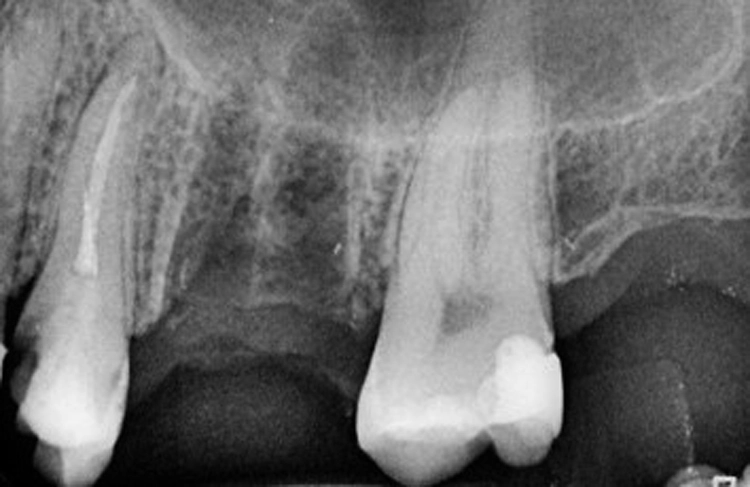

Nach der Pilotbohrung wird das Implantatbett mit Condensern in aufsteigenden Durchmessern aufbereitet. Erreicht man mit einem Condenser „handfest“ eine Stabilität von 20 Ncm, so wird ein Implantat mit dem nächstgrößeren Durchmesser inseriert. Die Bilder (Abbildungen 4a-h) zeigen das Beispiel einer Sofortimplantation regio 16.

Dr. Volker Knorr, Eislingen

Es wurde ein Champions (R)Evolution-Implantat ø 4,5 mm – L 8 mm in Verbindung mit einem internen, direkten Sinuslift (IDS) inseriert. Mit dem Condenser ø 3,8 mm wurden „handfest“ (etwa 20 Ncm) erreicht und deshalb ein Implantat ø 4,0 mm inseriert. Hätte man die Stabilität erst mit dem Condenser ø 5,3 mm erreicht, so hätte man ein Champions (R)Evolution-Implantat gleicher Länge, aber mit dem Durchmesser 5,5 mm einsetzen sollen.